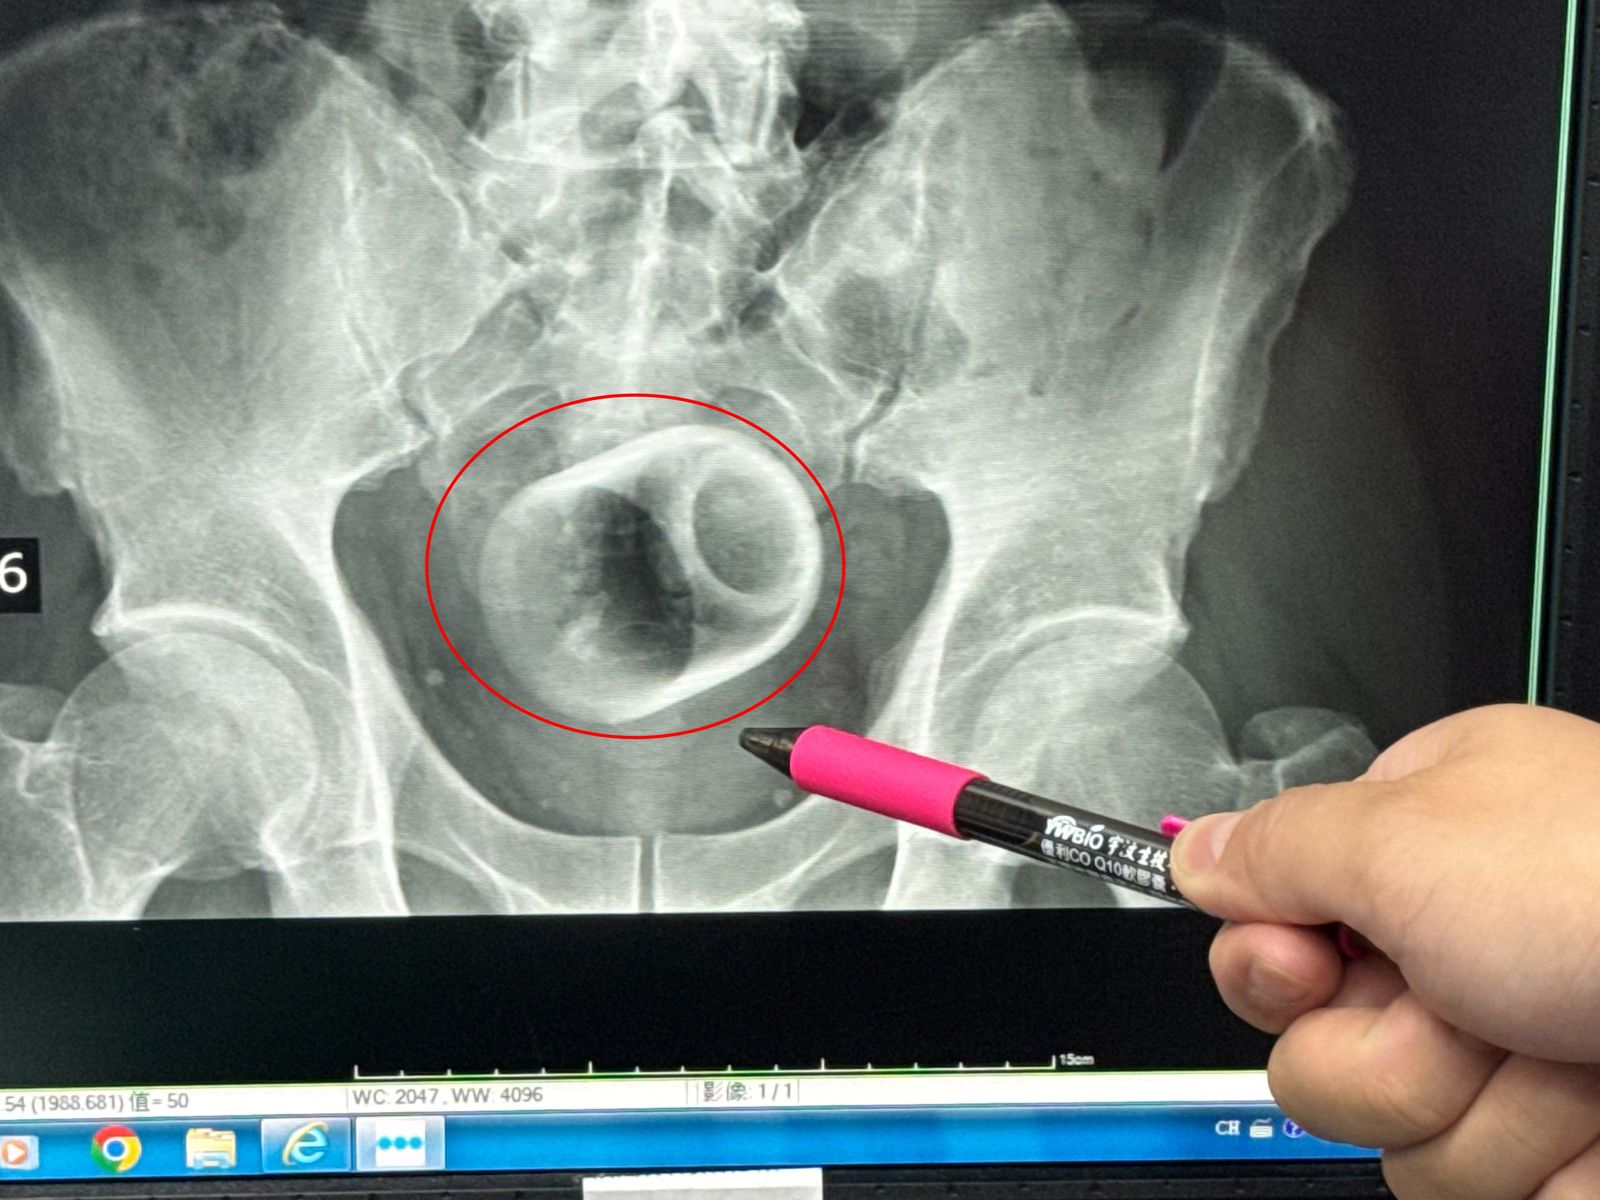

中部地區一名男子日前到醫院求診,自述已經3天無法排便。醫生幫他做了X光檢查之後,驚見男子的肛門竟然塞一個直徑約6公分、高約8公分的陶瓷杯!外科醫師原本要使用器械把杯子夾出來,但杯緣光滑無法施力,杯子全被大腸包住,部分腸子缺血也造成壞死,真的是超級慘!

男子到大甲李綜合醫院求診,駐診在李綜合醫院的台中榮總外科醫師吳坤達表示,該名患者到院時,自述3天都無法排便,但是可能是因為害羞,不敢告訴醫生自己的肛門塞了一個杯子,還是等到X光檢查,才發現男子的骨盆腔內有異物,發現是一個杯子,杯口朝下。